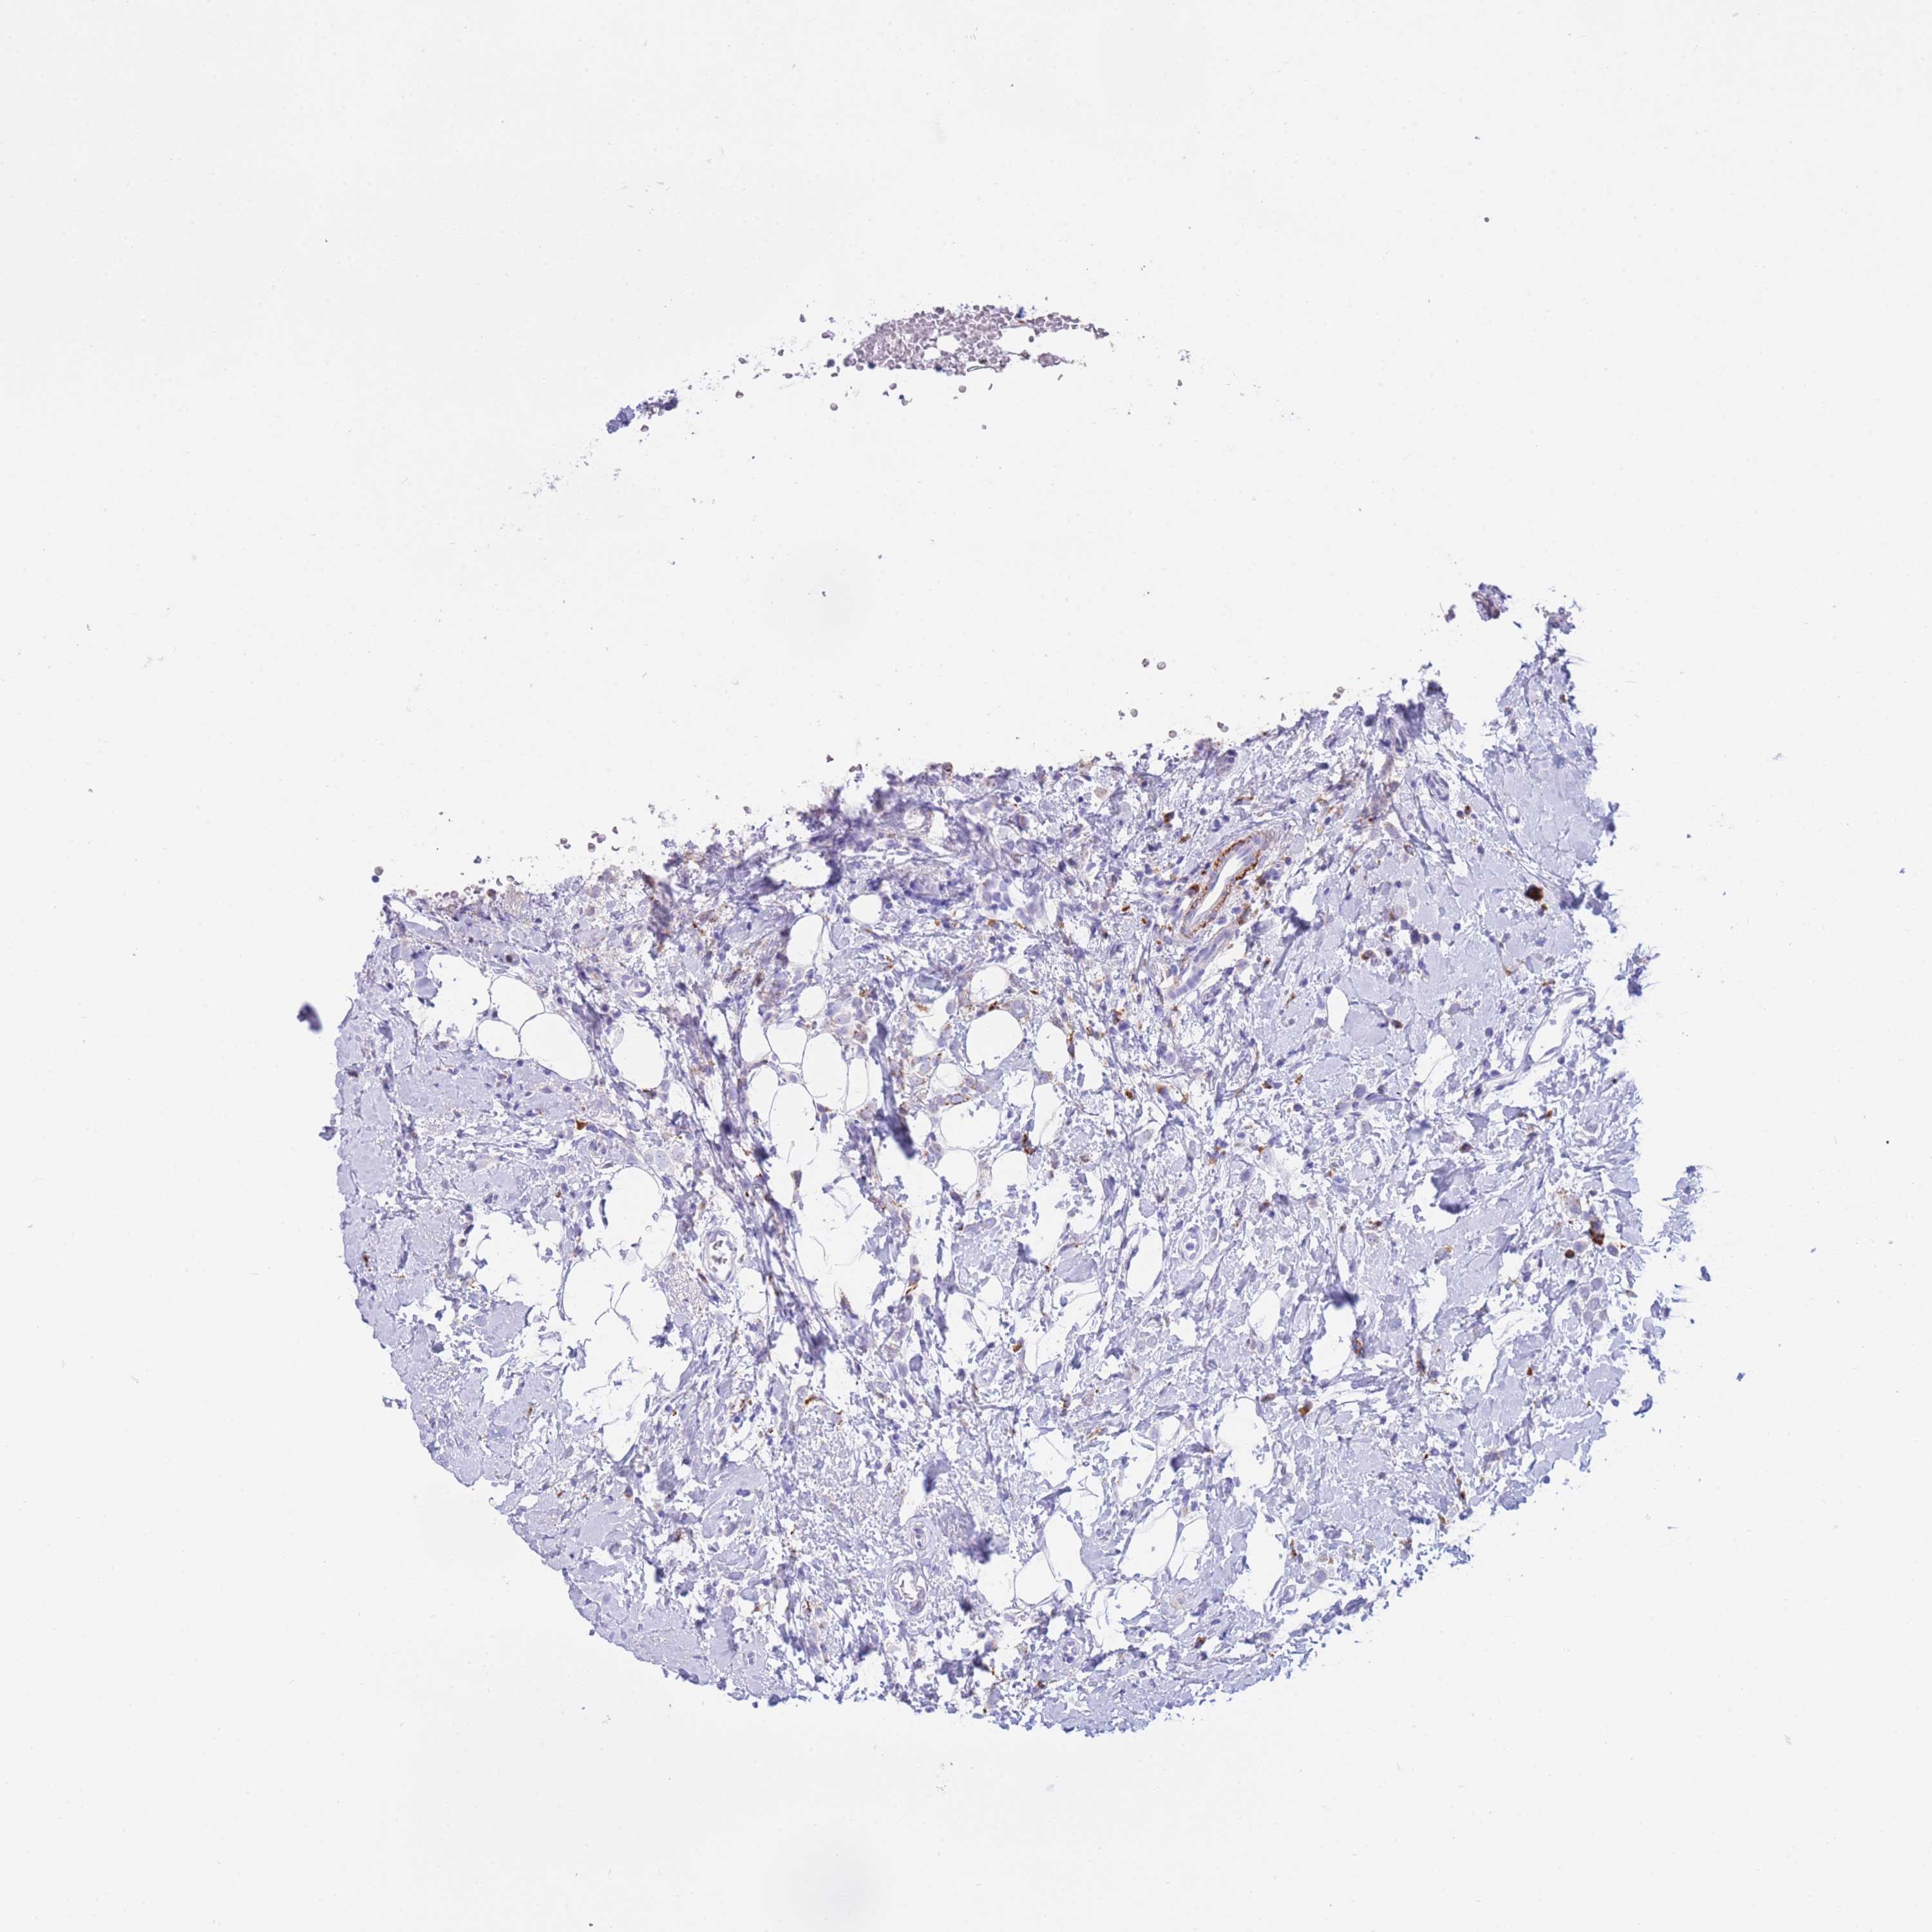

CANCER BREAST CANCER Show tissue menu

BRCA TCGA BRCA VALIDATION PROTEIN EXPRESSION

Breast cancer

Human cancer